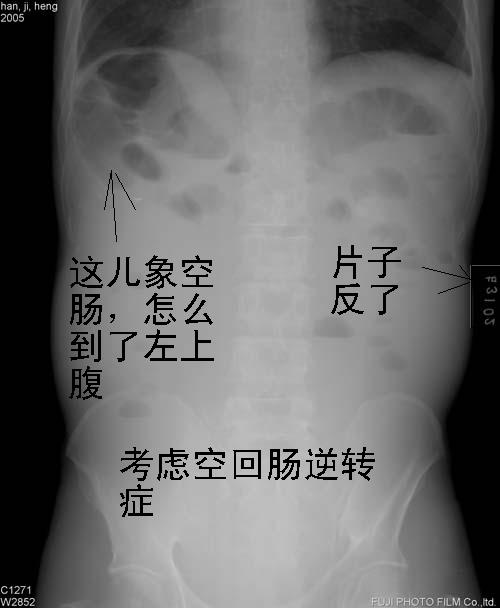

分析一下这个没有病史的腹平片.

片子放反了

可见多个短液平,小肠不全梗阻??

盆腔区域未见肠气影且双侧胁腹线模糊不清,结肠影上移,腹部多个短小气液平面,考虑腹膜炎腹水可能,建议做b-us检查

若不是图片放反了,考虑病人内脏反位。

病人呈“蛙状腹”,双侧胁腹脂肪线模糊不清,肝三角消失,小肠内大量积液,可见多个小液平面。

考虑:腹腔积液,绞窄性肠梗阻不能排除,建议结合临床,超声进一步检查。

1.“蛙状腹”,肠曲内上移位,双侧胁腹脂肪线模糊不清_____系腹腔积液表现.

2.小肠扩张积液积气,以积液为主.没有卧位片,难以判断结肠情况(观察肠梗阻,应常规立卧位).

a.如结肠有积液积气,肠梗阻应该是麻痹性的,是腹膜刺激引起的 .

b.如结肠没有积液积气,当考虑小肠梗阻.

做个ct非常有助于诊断(常可查明梗阻原因)